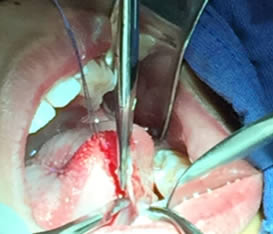

• Se realizó una incisión horizontal en la parte media del frenillo con hoja de bisturí No. 15 y mango No. 3, posteriormente se comenzó a cortar el frenillo de arriba abajo cuidando la anatomía de la región y la zona de las carúnculas sublinguales de los conductos de Wharton y Rivini. (Figuras 5 y 6).

Figuras 5 y 6. Incisión y corte del frenillo.